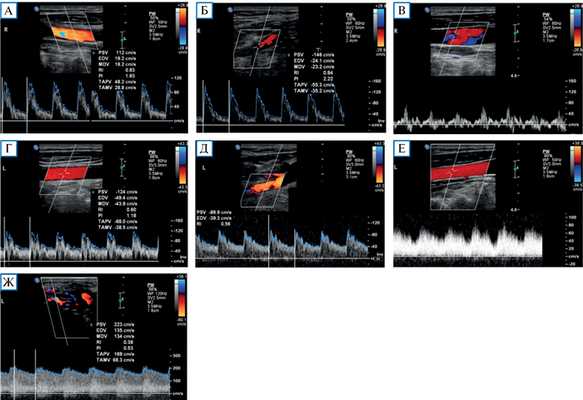

Проведенное дуплексное сканирование сосудов головы обнаружило признаки артериовенозной мальформации в бассейне левой наружной сонной артерии с артериализацией и усилением кровотока по внутренней яремной вене. Усиление скорости кровотока по задней околоушной артерии позволило предположить ее в качестве «питающего» сосуда (рис. 1). Контрастная МР-ангиография подтвердила наличие артериовенозного соустья с вовлечением поперечного и частично сигмовидного синусов слева (рис. 2).

Рис. 1. Дуплексное сканирование сосудов шеи

Примечание. Кровоток по общей сонной артерии (А) и наружной сонной артерии (Б) справа с нормальными индексами периферического сопротивления (PI и RI). Физиологический трехфазный кровоток по правой внутренней яремной вене (В). Кровоток по общей сонной артерии (Г) и наружной сонной артерии (Д) слева со сниженными индексами периферического сопротивления. Артериализация кровотока по левой внутренней яремной вене (Е). Значительно повышенный кровоток с низкими индексами периферического сопротивления по задней околоушной артерии (ветви наружной сонной артерии) в области артериовенозной мальформации (Ж).